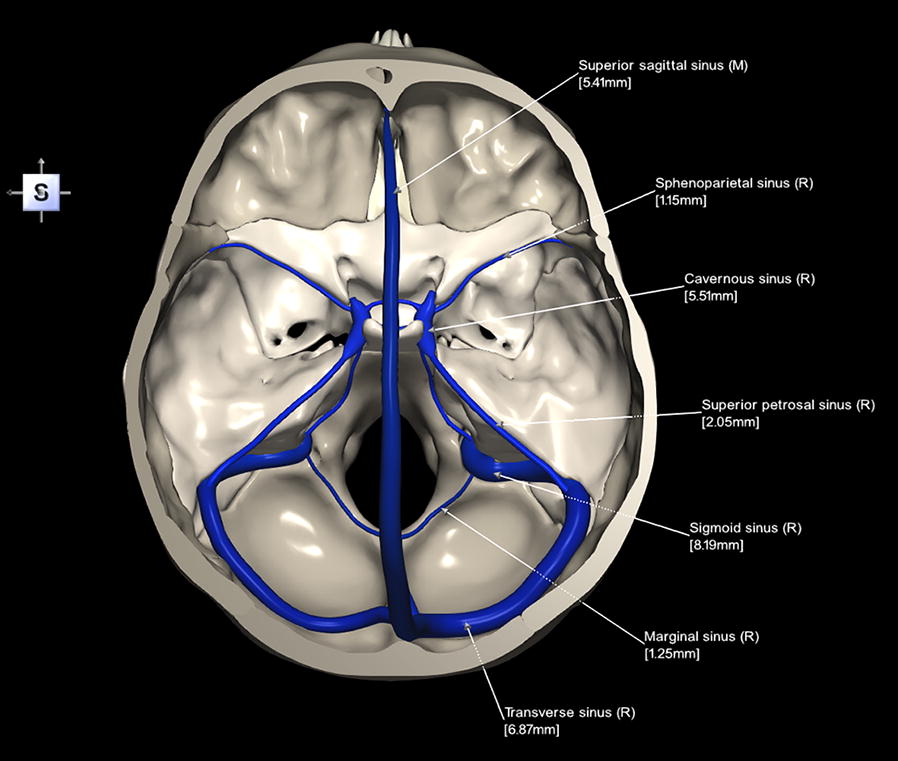

Dural Folds. - Dural Sinuses

Figure 13.16 Dural Sinuses and Veins Blood drains from the brain through a series of sinuses that connect to the jugular veins.

Main veins and sinuses of the human brain.

Dural Sinuses. - Wernicke’s Area, Broca’s Area, Aphasia, Dysphasia, Receptive (Fluent) Aphasia, Expressive (Non-fluent) Aphasia